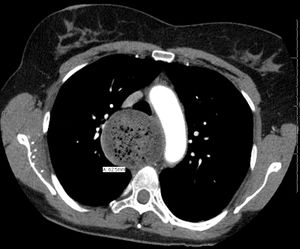

التشخيص

ابتلاع الباريوم

قياس الضغط المريئي

خزعة